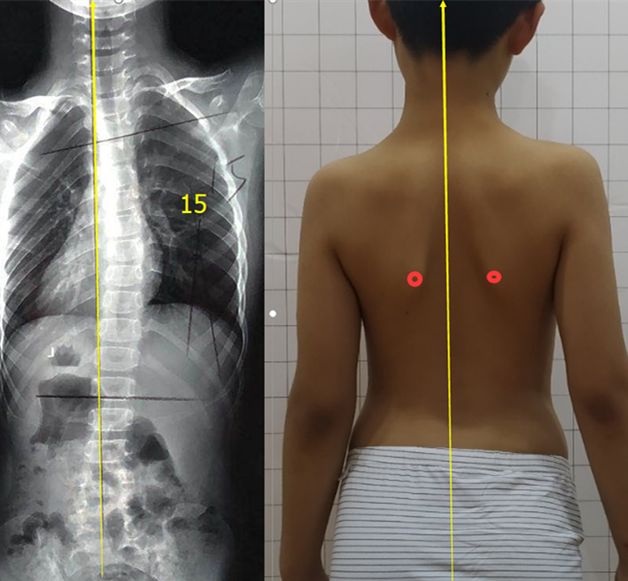

姿勢性脊柱側(cè)彎是由于不良姿勢導(dǎo)致的,通過拍片檢查,X線片顯示脊柱有偏移,cobb角度有的也超過10度,甚至有超過20度的。

姿勢性脊柱側(cè)彎又叫假性脊柱側(cè)彎,功能性脊柱側(cè)彎,是由于人體脊柱本身有側(cè)曲的功能,在拍片的一瞬間,采取了錯誤的站姿(或者平時的站姿就不好),導(dǎo)致片子上看到了側(cè)彎的存在。但測量剃刀背,度數(shù)在5度以內(nèi)(正常范圍),并沒有因椎體旋轉(zhuǎn)導(dǎo)致的肋骨變形,這樣的側(cè)彎,一般只需要觀察即可。

所以,姿勢性脊柱側(cè)彎只是脊柱在額狀面發(fā)生了偏移,并沒有在水平面發(fā)生旋轉(zhuǎn)畸形,還不是脊柱的三維畸形。這個時候就需要明確診斷,定期復(fù)查即可。不需要支具和矯形體操來干預(yù)。